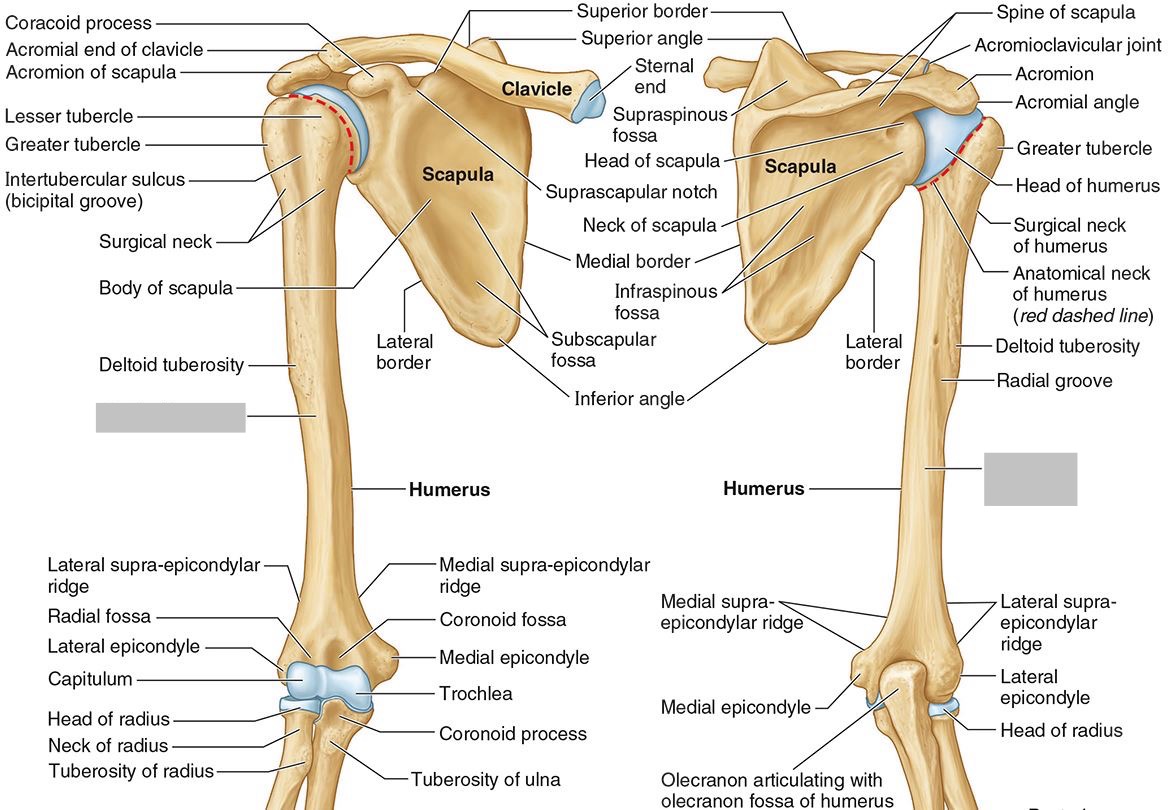

What part of the humerus is this?

The head of the humerus articulates with the scapula at the glenohumeral joint.

What part of the humerus is this?

The anatomic neck is an indentation distal to the head and provides an attachment for the fibrous joint capsule of the glenohumeral joint.

What part of the humerus is this?

The greater tubercle lies lateral and distal to the anatomic neck.

What part of the humerus is this?

The lesser tubercle lies on the anterior/medial side of the humerus, just distal the anatomic neck.

What part of the humerus is this?

The intertubercular (bicipital) groove lies between the greater and lesser tubercles.

What part of the humerus is this?

The surgical neck is a narrow area distal to the tubercles. It is a common site for proximal humerus fractures.

What part of the humerus is this?

The humeral shaft features the deltoid tuberosity laterally for the distal insertion of the deltoid muscle.

What part of the humerus is this?

The radial groove is an oblique depression that contains the radial nerve and deep brachial artery.

Which parts of the humerus is this?

The medial and lateral epicondyles are distal prominences to which many forearm tendons attach, near the elbow joint.

Which parts of the humerus is this?

The medial and lateral supracondylar ridges extend superiorly from the medial and lateral epicondyles.

Which parts of the humerus is this?

The trochlea and the capitulum (the condyles) are the most distal surfaces of the humerus, where it articulates with the forearm bones at the elbow joint

What part of the humerus is this?

The olecranon fossa is a posterior depression above the trochlea that receives that olecranon process of the ulna

What part of the humerus is this?

The coronoid fossa is an anterior depression above the trochlea that receives that coronoid process of the ulna.